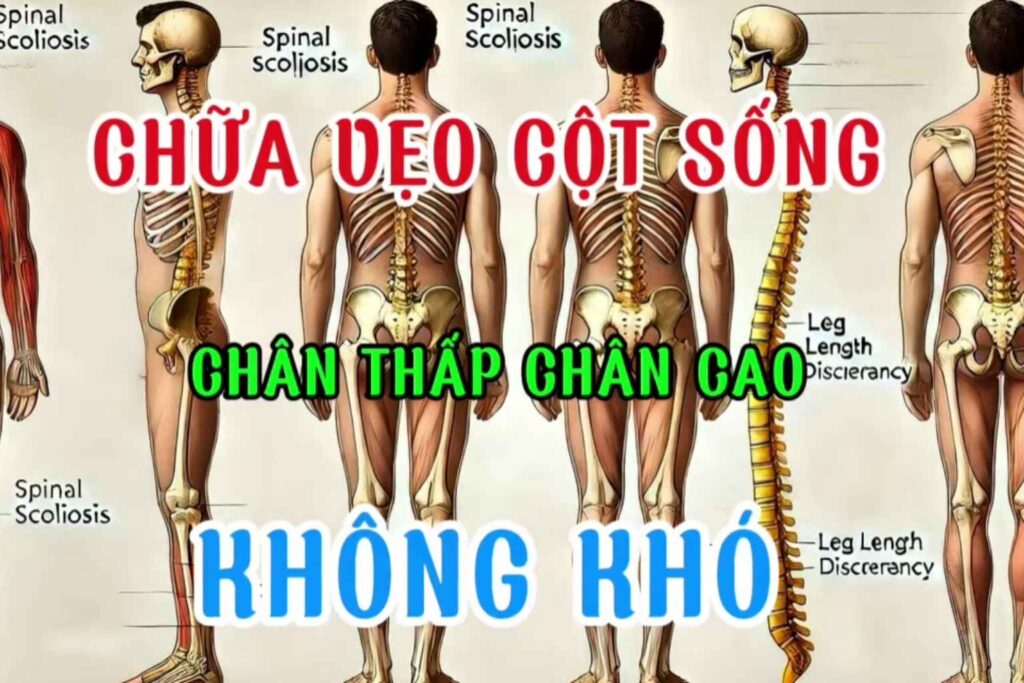

Cơ thể con người không hoàn toàn đối xứng, và trong cuộc sống hàng ngày, chúng ta thường vô thức lặp lại những thói quen vận động không cân bằng. Điều này có thể dẫn đến sự mất cân xứng cơ bắp, gây áp lực lên khớp và tạo ra các vấn đề về cột […]